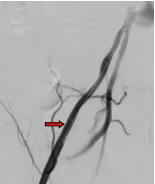

患者,女,50岁,主因腹膜后恶性肿瘤术后出现引流管出血逐渐增加,转入我科行介入治疗,造影提示:右侧髂外动脉中段造影剂外渗、局部大片造影剂滞留,考虑髂外动脉破裂出血,行4*40mm球囊以6atm压迫止血后造影出血明显减少,遂行髂外动脉覆膜支架植入术彻底解决患者出血问题,为患者后续治疗。

术前造影 球囊压迫止血后造影 支架植入术后